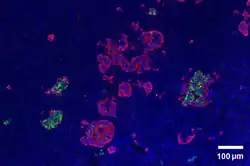

The pancreas serves multiple roles within mammalian organisms. It plays a role in the digestive system and the endocrine system making it an organ and a very important gland.[2] PP cells tend to located in the pancreatic islets, and are one of the rarer pancreatic cell types.[1] Some small clusters may also be found surrounded by exocrine pancreas.[3] They tend to be located in the duodenal part of the pancreas more medially.[3] Given their location in pancreatic islets along with their low population, they are able to respond efficiently to changes in blood sugar, nerve impulses, and chemical signaling through gap junctions or cellular signaling. PP cells show the highest concentration at the head of the pancreas.[1]

Through different microscopy techniques, the structural related details of PP cells have been able to be better understood. This is inclusive of how big they are, what their cellular membranes look like, the proteins associated with them, and even their size. PP cells are elongated cells. Another one of these details can be noted in insulins secretory granules, or container like buds, that store insulin within a cell. In PP cells, the size of the insulin granules are smaller and spherical and similar to those in alpha cells. This is noted in human PP cells, but different animals have been shown to have different sized granules compared to humans, like rodents. In cats and dogs, PP cells have large granules.[6] In rats, PP cells have few granules, similar to humans. In dogs, some PP cells are located in the walls of the antrum of the stomach.[3]